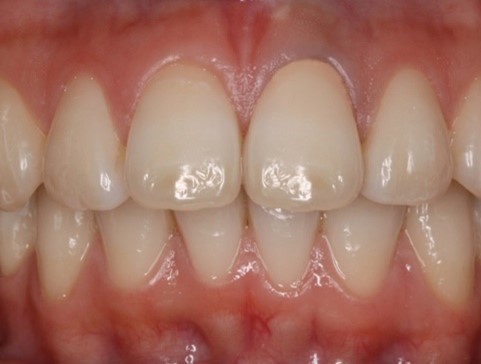

オールセラミッククラウン(ジャケットタイプ)

二ケイ酸リチウムガラスやジルコニアを使用したクラウンです。歯肉が黒ずみにくく、高い強度と生態親和性があります。金属を使用しません。

〈実際の症例:20代の女性。上顎前歯部への補綴治療〉

治療後

治療内容:上顎の前歯4本にオールセラミッククラウン(ジャケットタイプ)を被せ、審美的な回復をしました。

治療期間・回数:約6か月間、10回

費用(自由診療となります):484,000円

リスク・副作用:オールセラミッククラウンの脱離や破折、咬合違和感